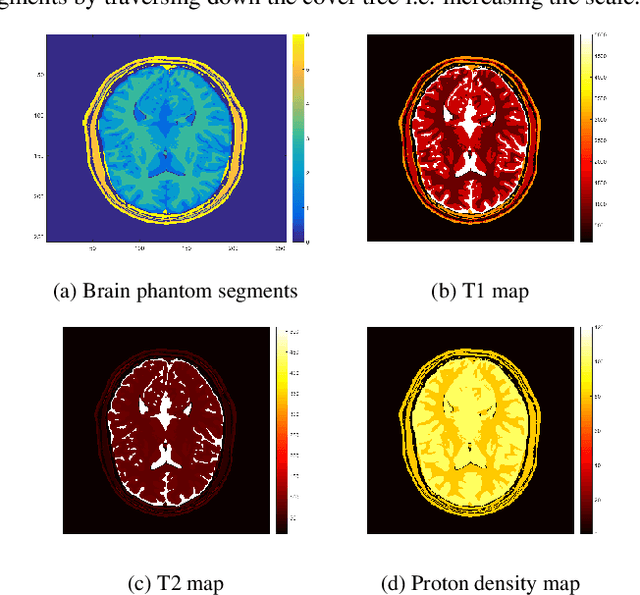

Abstract:Current popular methods for Magnetic Resonance Fingerprint (MRF) recovery are bottlenecked by the heavy computations of a matched-filtering step due to the growing size and complexity of the fingerprint dictionaries in multi-parametric quantitative MRI applications. We address this shortcoming by arranging dictionary atoms in the form of cover tree structures and adopt the corresponding fast approximate nearest neighbour searches to accelerate matched-filtering. For datasets belonging to smooth low-dimensional manifolds cover trees offer search complexities logarithmic in terms of data population. With this motivation we propose an iterative reconstruction algorithm, named CoverBLIP, to address large-size MRF problems where the fingerprint dictionary i.e. discrete manifold of Bloch responses, encodes several intrinsic NMR parameters. We study different forms of convergence for this algorithm and we show that provided with a notion of embedding, the inexact and non-convex iterations of CoverBLIP linearly convergence toward a near-global solution with the same order of accuracy as using exact brute-force searches. Our further examinations on both synthetic and real-world datasets and using different sampling strategies, indicates between 2 to 3 orders of magnitude reduction in total search computations. Cover trees are robust against the curse-of-dimensionality and therefore CoverBLIP provides a notion of scalability -- a consistent gain in time-accuracy performance-- for searching high-dimensional atoms which may not be easily preprocessed (i.e. for dimensionality reduction) due to the increasing degrees of non-linearities appearing in the emerging multi-parametric MRF dictionaries.

Abstract:Current proposed solutions for the high dimensionality of the MRF reconstruction problem rely on a linear compression step to reduce the matching computations and boost the efficiency of fast but non-scalable searching schemes such as the KD-trees. However such methodologies often introduce an unfavourable compromise in the estimation accuracy when applied to nonlinear data structures such as the manifold of Bloch responses with possible increased dynamic complexity and growth in data population. To address this shortcoming we propose an inexact iterative reconstruction method, dubbed as the Cover BLoch response Iterative Projection (CoverBLIP). Iterative methods improve the accuracy of their non-iterative counterparts and are additionally robust against certain accelerated approximate updates, without compromising their final accuracy. Leveraging on these results, we accelerate matched-filtering using an ANNS algorithm based on Cover trees with a robustness feature against the curse of dimensionality.